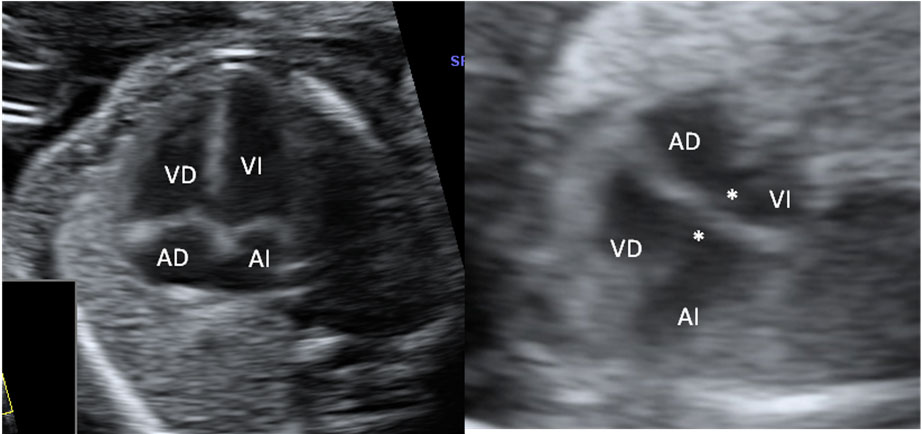

En la ecografía podemos ver una hernia intestinal (u onfalocele), lo que significa que parte del intestino del feto está fuera del abdomen. Observamos la sección transversal del abdomen fetal. A la izquierda, contenido intestinal (entre marcas de medición) herniado fuera del abdomen, debido a un defecto en la inserción del cordón umbilical, que se marca en la imagen con una estrella (*).